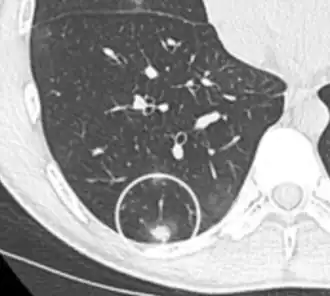

- Areas of fatty tissue (−40 to −120 HU) indicates a hamartoma. However, only about 50% of hamartomas are fat containing.[9]

-

Low attenuating nodule (in this case a fat containing hamartoma).[9] -

Cavitation with relatively thick wall, in this case aspergilloma).[9]

- In case of calcifications, a popcorn-like appearance indicates a hamartoma, which is benign.[3]